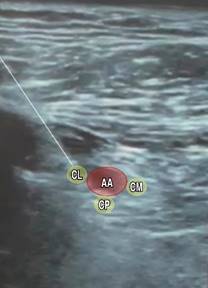

Para la anestesia regional se realizó primero el bloqueo del plexo braquial supraclavicular izquierdo ecoguiado, con el paciente en decúbito supino, en posición semifowler a 30o, la cabeza rotada hacia el lado derecho, transductor lineal de alta frecuencia (8-12 Mhz) en región supraclavicular paralelo a la clavícula, se identifica arteria subclavia, reborde de la primera costilla, pleura y divisiones del plexo braquial; en plano longitudinal se incide con aguja de neuroestimulación de 100 mm hasta el Corner Pocket; se infiltran 15 mL de ropivacaína al 0.5%, visualizando hidrodisección (Figura 1). El bloqueo del plexo braquial infraclavicular derecho ecoguiado fue el segundo bloqueo, con el paciente en posición semifowler, la cabeza rotada hacia el lado izquierdo; en plano parasagital justamente medial al proceso coracoides sobre la región pectoral colocamos el transductor lineal de alta frecuencia (8-12 Mhz); se localiza arteria axilar, vena axilar y cordones lateral, posterior y medial del plexo braquial, profundo a los músculos pectorales mayor y menor, se incide en plano longitudinal con aguja de neuroestimulación de 100 mm; se infiltran 15 mL de ropivacaína al 0.5%, visualizando hidrodisección (Figura 2).